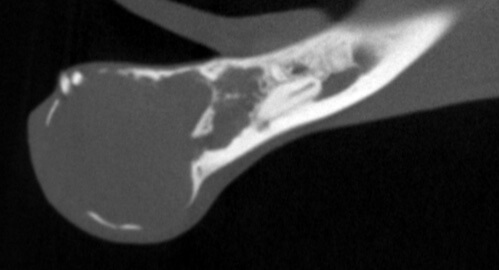

Bilateral rostral mandibulectomy to excise an oral mass that is suspected to be benign (not spreading) but locally invasive. Oral surgical removal of unerupted/impacted lower left canine tooth occupying the majority of the left mandible.

Cystic rostral mandibular swelling associated with unerupted 304. Adopted in Sept as intact male, estimate age 2. RDVM neutered and found mild swelling and unerupted 304 (lower left canine tooth). Swelling increased since adoption.

The canine tooth was not missing, but was impacted present in the middle of the left mandible. A tumor was present requiring removal of the tumor and associated impacted tooth.

We scaled, polished, performed 3D imaging and intraoral radiographs (x-rays), and confirmed the presence of an oral mass. The mass effect appears to have enlarged and extended to the lower right canine tooth.

As previously noted, the lower left canine tooth was unerupted and impacted into the center of the mandible. The cyst growth/mass effect has caused haphazard tissues to be present around all of the incisors.